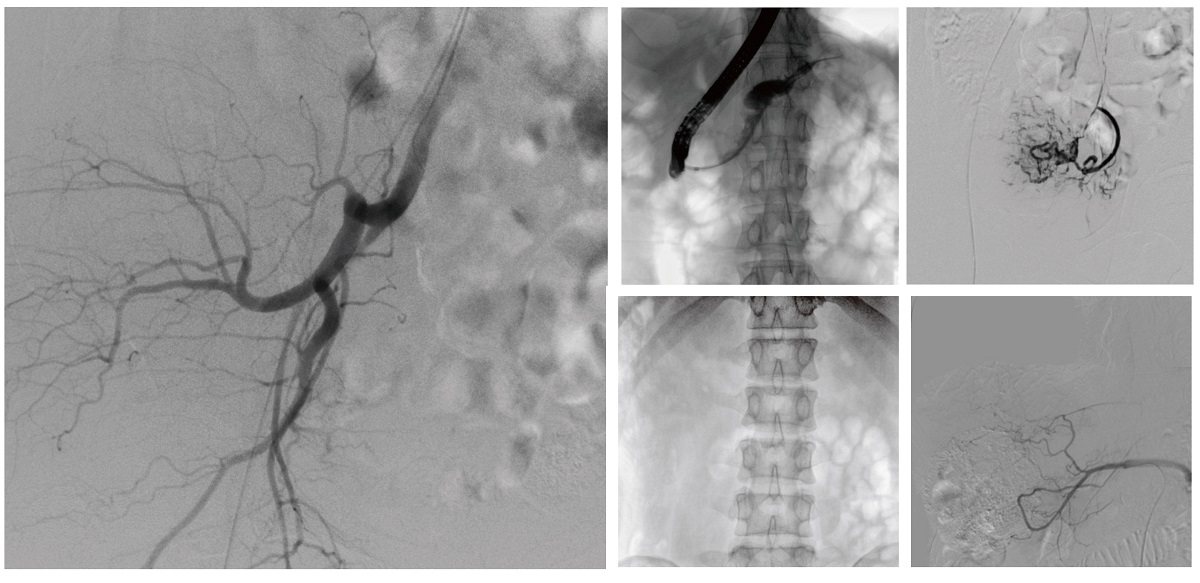

醫(yī)院引進(jìn)的普愛醫(yī)療移動式平板介入中C,其高清成像能力覆蓋骨科、介入科、泌尿外科、婦產(chǎn)科等多科室,能夠滿足介入微創(chuàng)手術(shù)的多樣化需求。

設(shè)備的移動式設(shè)計,無需對現(xiàn)有手術(shù)室進(jìn)行改造,適合高負(fù)荷手術(shù)量或應(yīng)急情況下的靈活部署。如在急診介入手術(shù)中,該設(shè)備能迅速響應(yīng)需求,為醫(yī)生提供實時影像支持,提升搶救效率。